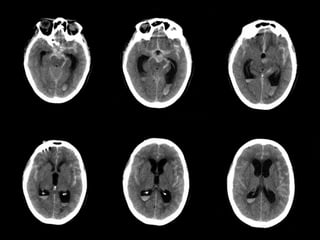

Bonus case  Mr.LR is a 80 y/o male presenting with:  3 month history of delirium  Recent fall from bed  Large scalp laceration  No focal neurological findings  An non-contrast CT scan of his brain is performed

• 70.

Subdural Look closely atthe midline structures Hint?

• 71.

Analysis  Can youspot the abnormalities?  What is your impression?  What would be your top diagnosis?

• 72.

Bonus case -Answer  Mr. LR had a tiny right-sided subdural hematoma  Blood is seen along the left subdural space as well as in the falx cerebri anteriorly (arrows)  The hematoma is acute  Because of its small size, no immediate treatment was required  Follow-up CT scans showed resolution of the subdural hematoma Normal scan for comparison